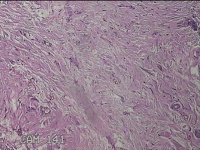

右颈部皮肤肿物

性别

女

年龄

29岁

临床诊断

纤维瘤

一般病史

右颈部皮肤起肿物10年左右。

标本名称

大体所见

灰白暗红色肿物0.3x0.2x0.1cm一个,表面光滑。

图2